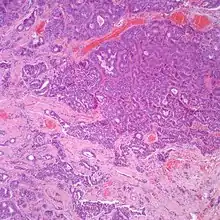

At the time of surgery, the tumor tends to peel away from the adjacent bones, although not the ossicles. It is usually fragmented, soft, rubbery and white to gray-tan. Due to the anatomic confines of the region, tumors are usually <1 cm.[8] The tumors arise below the surface, are unencapsulated, and have an infiltrative pattern of growth, composed of many different patterns (glandular, trabecular, cords, festoons, single cells). The tumor shows duct-like structures with inner luminal, flattened cells and outer, basal, cuboidal cells. The cells may have an eccentrically placed nucleus. The nuclear chromatin distribution is "salt-and-pepper", giving a delicate, fine appearance. Nucleoli are small with inconspicuous mitoses. There may be secretions in the gland tumor. It is possible to see a concurrent cholesteatoma.[2]